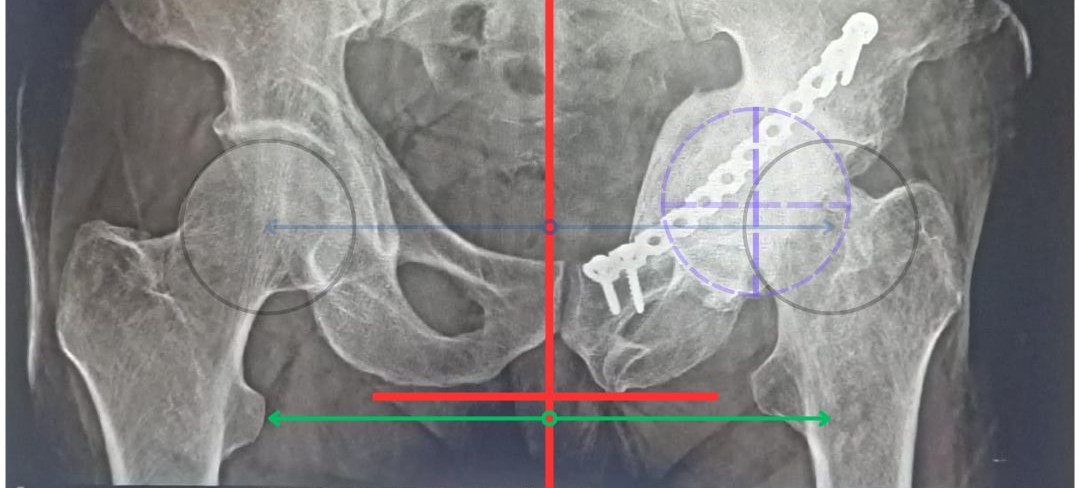

We got an X-ray and CT scan done and diagnosed him with Protusio Acetabuli. Due to the complexity, we planned a Total Hip Replacement (THR) using special revision implants – just in case we needed more support during surgery.

The patient underwent a modular revision hip replacement, and everything went well. Post-surgery, he showed good recovery, improved movement, relief from pain, and regained leg length.